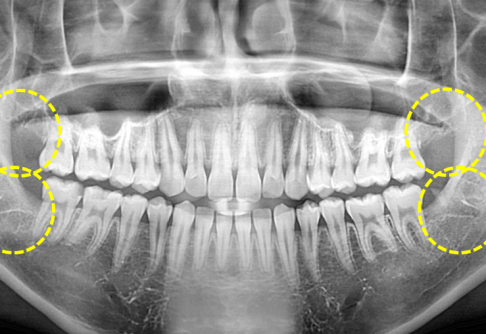

3D 장비를 통한

정밀 진단 시스템

디지털 장비 구축

대학병원 가지 않아도

일반∙매복사랑니 발치

사랑니발치 클리닉